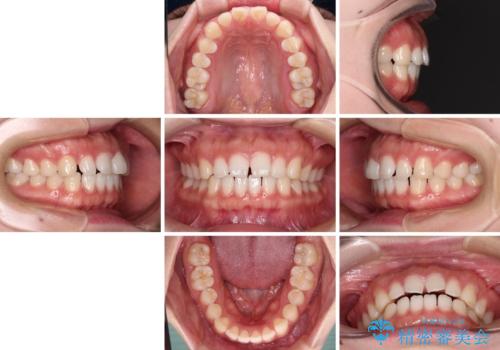

すきっ歯とオープンバイト インビザライン・ライトで改善

- 20代女性

- インビザライン・ライト

- 9ヶ月

- 食いしばりによる顎の負担を気にして来院された患者様です。

当初は、ボツリヌス毒素による咬筋の過緊張の緩和と、睡眠時のマウスピース装着による咬合負担の解消を行いました。

オープンバイトのため、奥歯に負担のかかる咬合状態であったので、矯正治療を提案したところ、希望をされました。

すきっ歯程度の軽度の歯列不正であったため、インビザライン・ライトにより咬合改善を行うこととしました。

オープンバイトやすきっ歯は、舌突出癖によりあっという間に後戻りをするため、矯正治療前からトレーニングを行っていただき、更には後戻り防止のワイヤーリテーナーを併用しています。